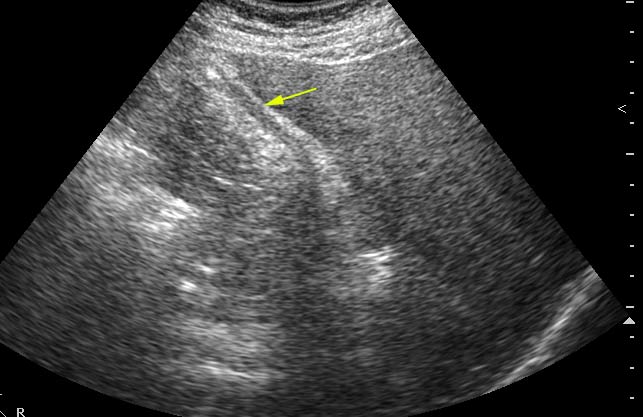

Похожий случай. Молодой мужчина, врач, длительные терпимые боли в правом подреберье.

???

2.По второму случаю можно было бы просто подумать о гиперкинезии ж.пузыря,который сокращается и "от глотка слюны".Но,прочитав эту фразу:"In patients with hilar cholangiocarcinoma and complete obstruction of both rigt and left hepatic ducts,extrahepatic bile ducts and the gollbladder appear empty(colapsed)",учитывая сложность выявления "малых" опухолей печени методом УЗИ,я думаю,что надо сделать КТ.